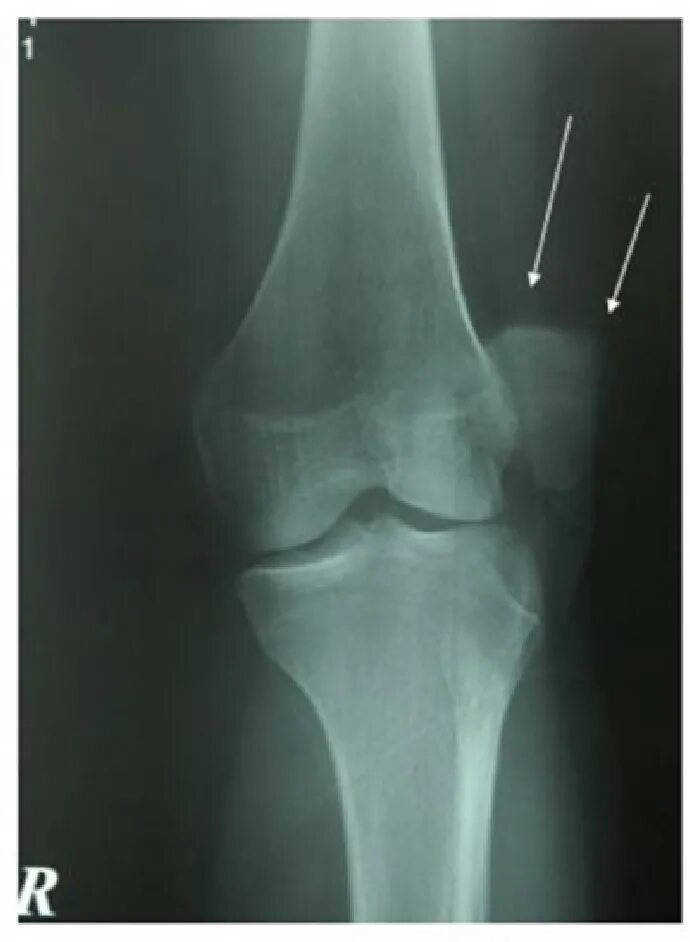

Смещение колена